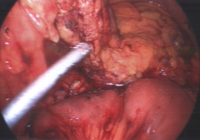

With many years experience as a liver transplant surgeon, Dr. de la Torre was the first to perform a major liver resection laparoscopically in the state of New Jersey, and has been performing laparoscopic liver surgery since 2007. Dr. de la Torre has 25 years of experience in surgery of the liver, pancreas, bile ducts, management of cirrhosis, portal hypertension, and liver cancer. Dr. De la Torre specializes in tissue sparing laparoscopic liver surgery in patients with cirrhosis, allowing the possibility of avoiding liver transplant for tumors located in the liver that were once deemed not feasible to remove. Dr. de la Torre published "

A Sling Technique For Laparoscopic Resection of Segment Seven of the Liver" in the Journal of the Society of Laparoendoscopic Surgery 2018 Apr-Jun; 22(2) and most recently "Sling Technique for Laparoscopic Liver Mobilization" Journal of the Society of Laparoscopic and Robotic Surgeons 2024 Apr-Jun;28(2). While most other surgeons in New Jersey start laparoscopically and eventually open, 95% of our patients start laparoscopically and end laparoscopically without compromise in surgical quality or safety.